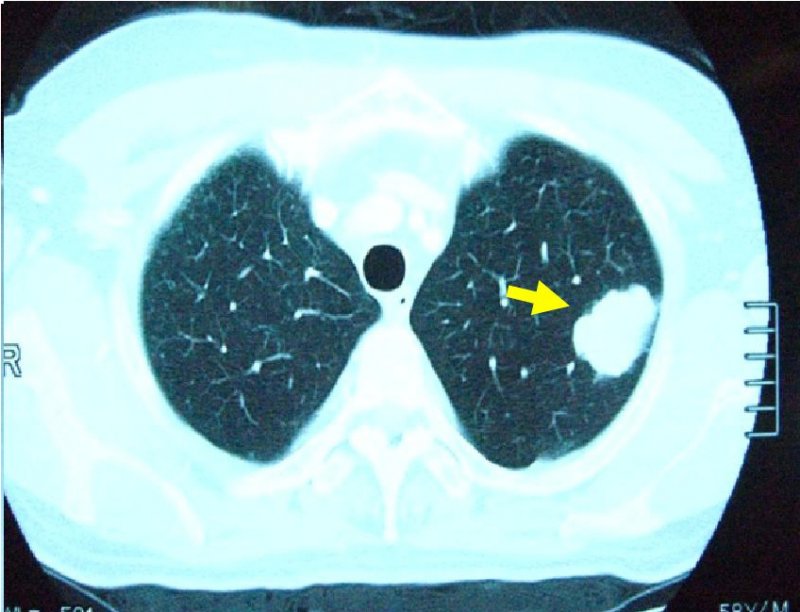

左肺癌の画像所見

胸部CT